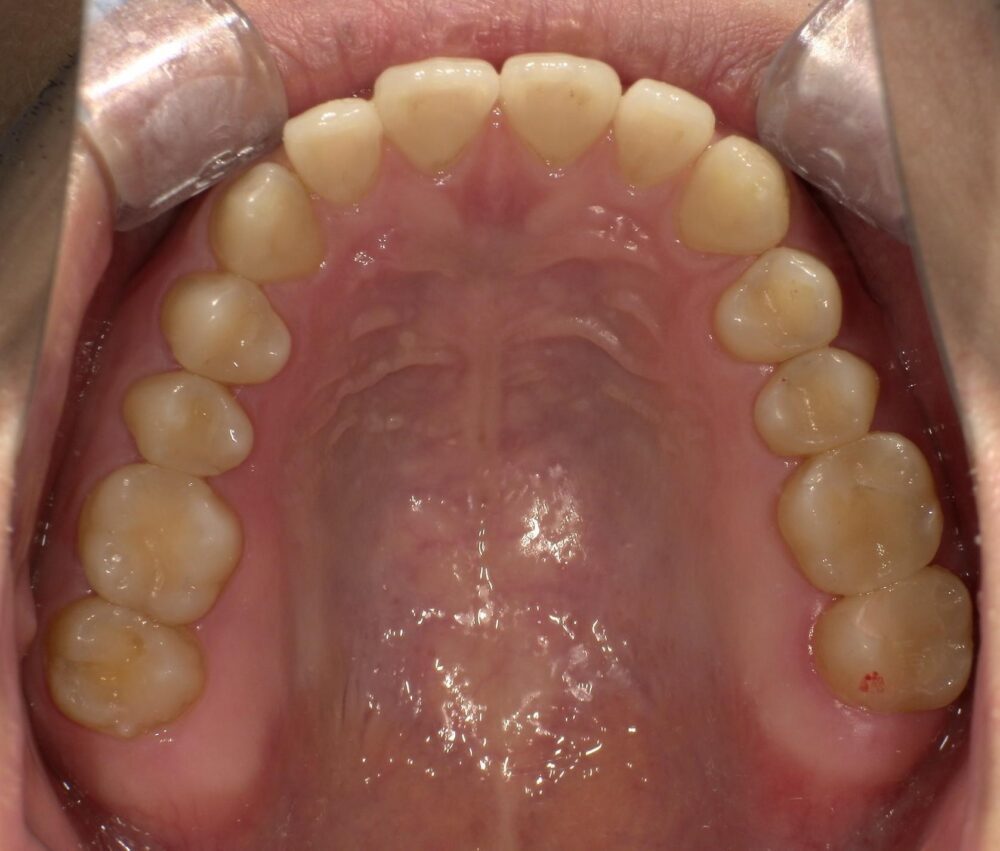

症例3

治療後

| 主訴 | 虫歯を治したい |

|---|---|

| 診断 |

2次虫歯 |

| 治療内容 | 保険CAD インレーによる修復治療 |

| 年齢・性別 |

29歳男性 |

| 治療期間 |

2ヶ月 |

| 治療費用 | 保険に準ずる。 |

| リスク・副作用 | CADの破折、着色 |